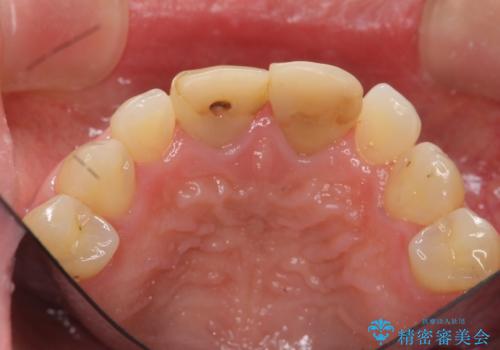

短期集中 前歯審美治療

- 3週間後に迫った結婚式までになんとか前歯をきれいにしたいという希望で来院されました。

ただ見えるクラウンを白くきれいにするのではなく、長期的な歯の予後を考えると根管治療・ファイバーコア築盛・精密な歯牙形成等クリアすべき条件は多々あると言えます。